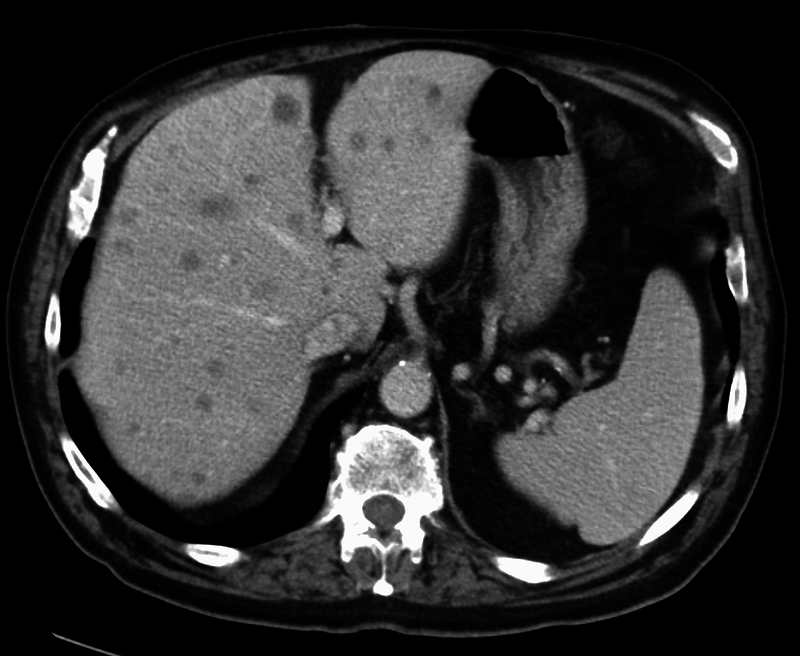

Compared to primary liver tumors, liver metastasis is more common.

Clinical diagnosis of liver metastasis may reveal a nodular free edge of the liver and hepatomegaly.

The most usual sources are liver metastasis are:

- Colon carcinomas

- Pancreatic carcinomas

- Lung cancers

- Breast cancer

Radiology of liver metastasis usually show numerous nodules in the liver.